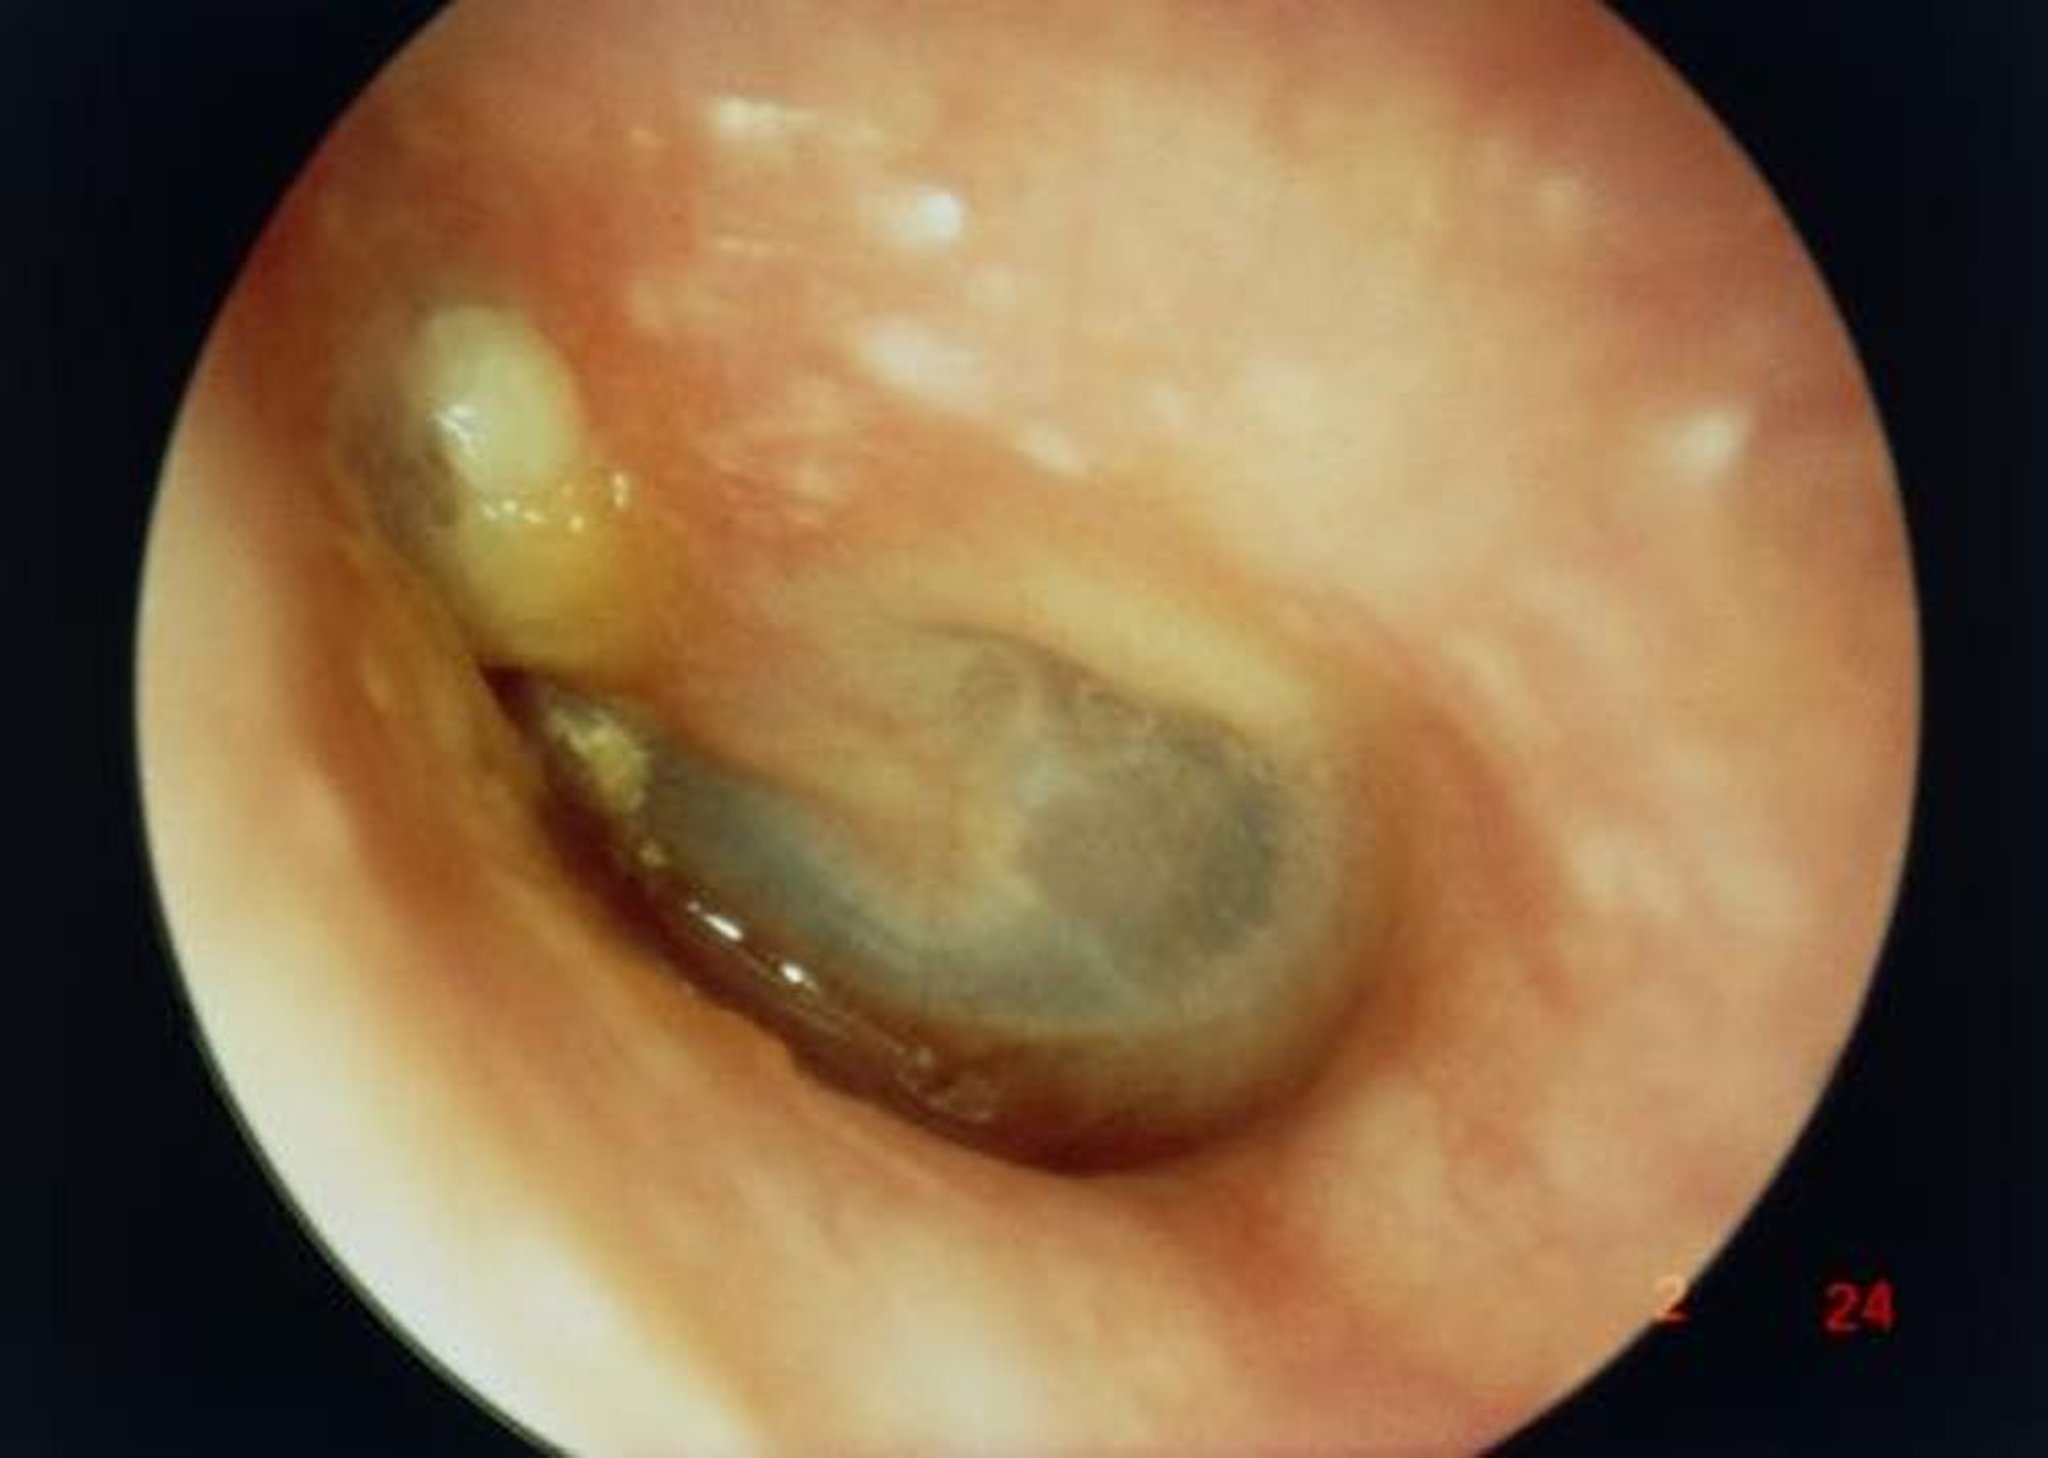

Холестеатома

На данном продольном изображении наружного ушного канала видна крупная холестеатома (белая опухоль слева выше короткого отростка молоточка), обусловленная перфорацией барабанной перепонки.